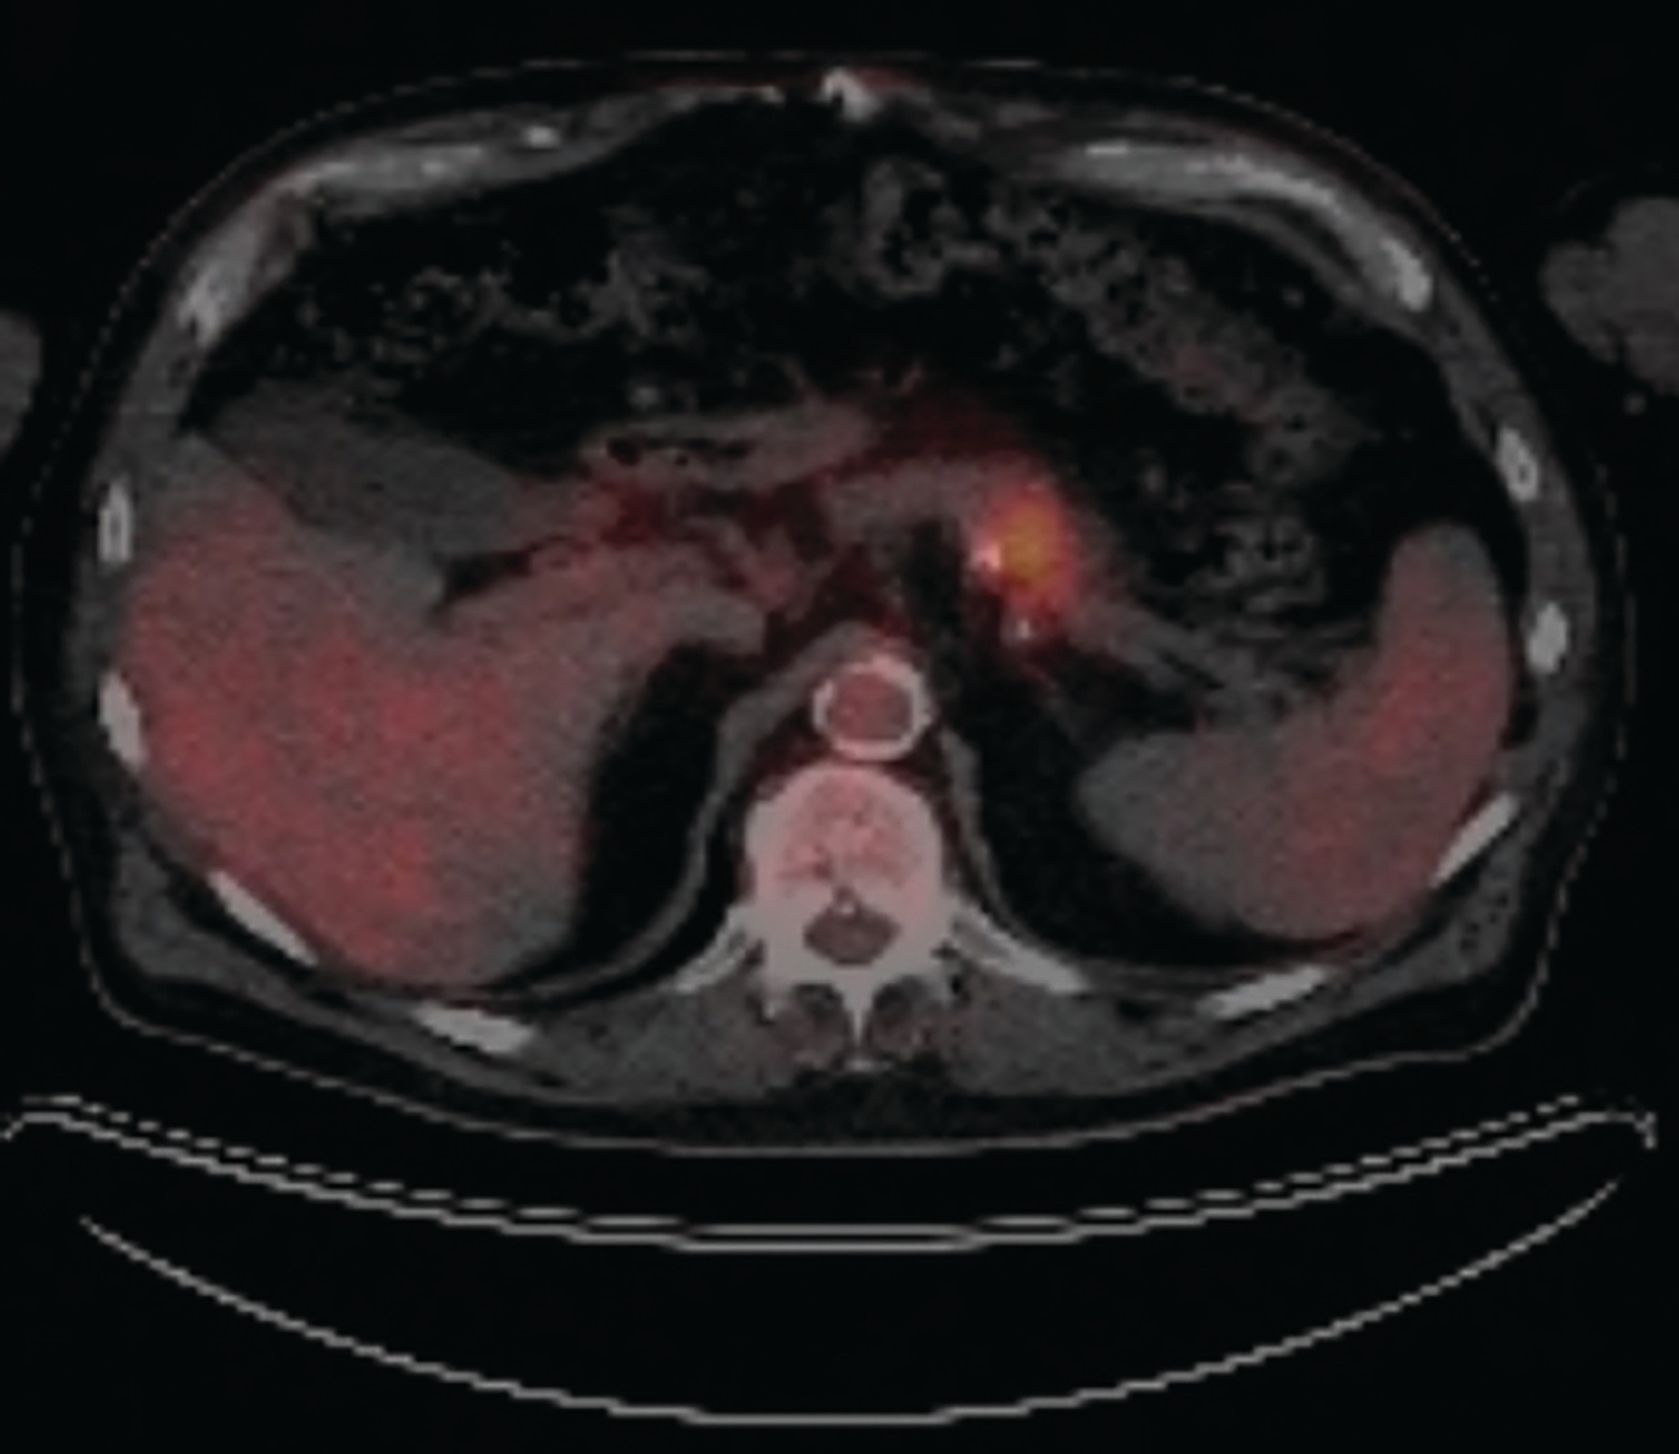

Figure 1. Positron emission tomography (PET) CT scan 8/1/19: small focus of increased fluorodeoxyglucose (FDG) activity within the pancreatic tail, suspicious for pancreatic malignancy measuring approximately 26 x 18 mm.

A Caucasian male, aged 74 years, was incidentally found to have a pancreatic mass during a surveillance imaging positron emission tomography (PET) scan for his prior malignant melanoma. The PET scan detected a suspicious uptake in the pancreatic tail corresponding to a subtle 2.6 cm x 1.8 cm region of low attenuation with a standardized uptake value of 7.5 (Figure 1). A CT scan of the abdomen revealed this to be a hypodense mass in the distal body/tail portion of the pancreas measuring 3.4 cm x 2.5 cm (Figure 2). Further work-up with upper endoscopy and endoscopic ultrasound biopsy revealed invasive PDAC. Family history was significant; his father and paternal grandfather had both received a diagnosis of PDAC around age 70 years and died from it. A genetic counseling visit and germline multigene hereditary pancreatic cancer panel testing detected no pathogenic sequence variants or deletions/duplications in the analyzed genes; these included APC, ATM, BRCA1, BRCA2, CDKN2A, MLH1, MSH2, MSH6, PALB2, PMS2, STK11, and TP53 (sequencing and deletion/duplication), and EPCAM (deletion/duplication only).